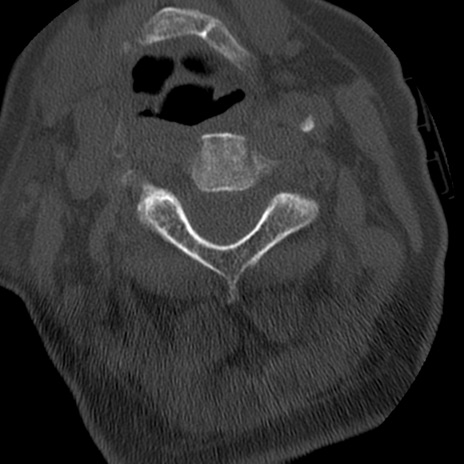

症例50 頚椎CT(横断像)

冠状断像

矢状断像